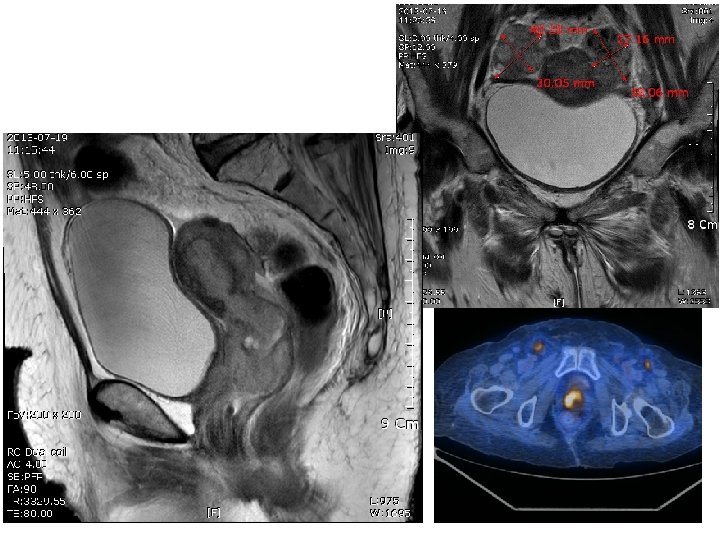

MR Imaging Findings: 1) Tumor visible as hyperintense mass on T 2 WI. 2) Tumor location: Mainly endocervix. 3) Vaginal infiltration : extension to lower one-third of vagina. 4) Uterine corpus invasion : myometrial invasion and both adnexal invasion. 5) Parametrial infiltration : irregular spiculated margin at the right stromal ring, suggesting right parametrial invasion. 7) Extend to bladder : Suspicious invasion of the posteior bladder wall via anterior vaginal fornix 8) Lymph nodes. : Metastatic lymph nodes at the both inguinal areas. 10) Ascites and peritoneal thickening with enhancing : C/W Peritoneal carcinomatosis. 11) 4 x 3 cm sized and 3. 8 x 2. 7 cm sized solid masses at the both ovaries, suggesting ovarian metastases, both. ====== [Conclusion] ====== 1. Cervix cancer, invasion to the lower vagina, right parametrium, uterine corpus, both adnexa and suspicious bladder wall with peritoneal carcinomatosis and metastatic lymphadenopathy at above mentioned sites. 2. Ovarian metastases, both.